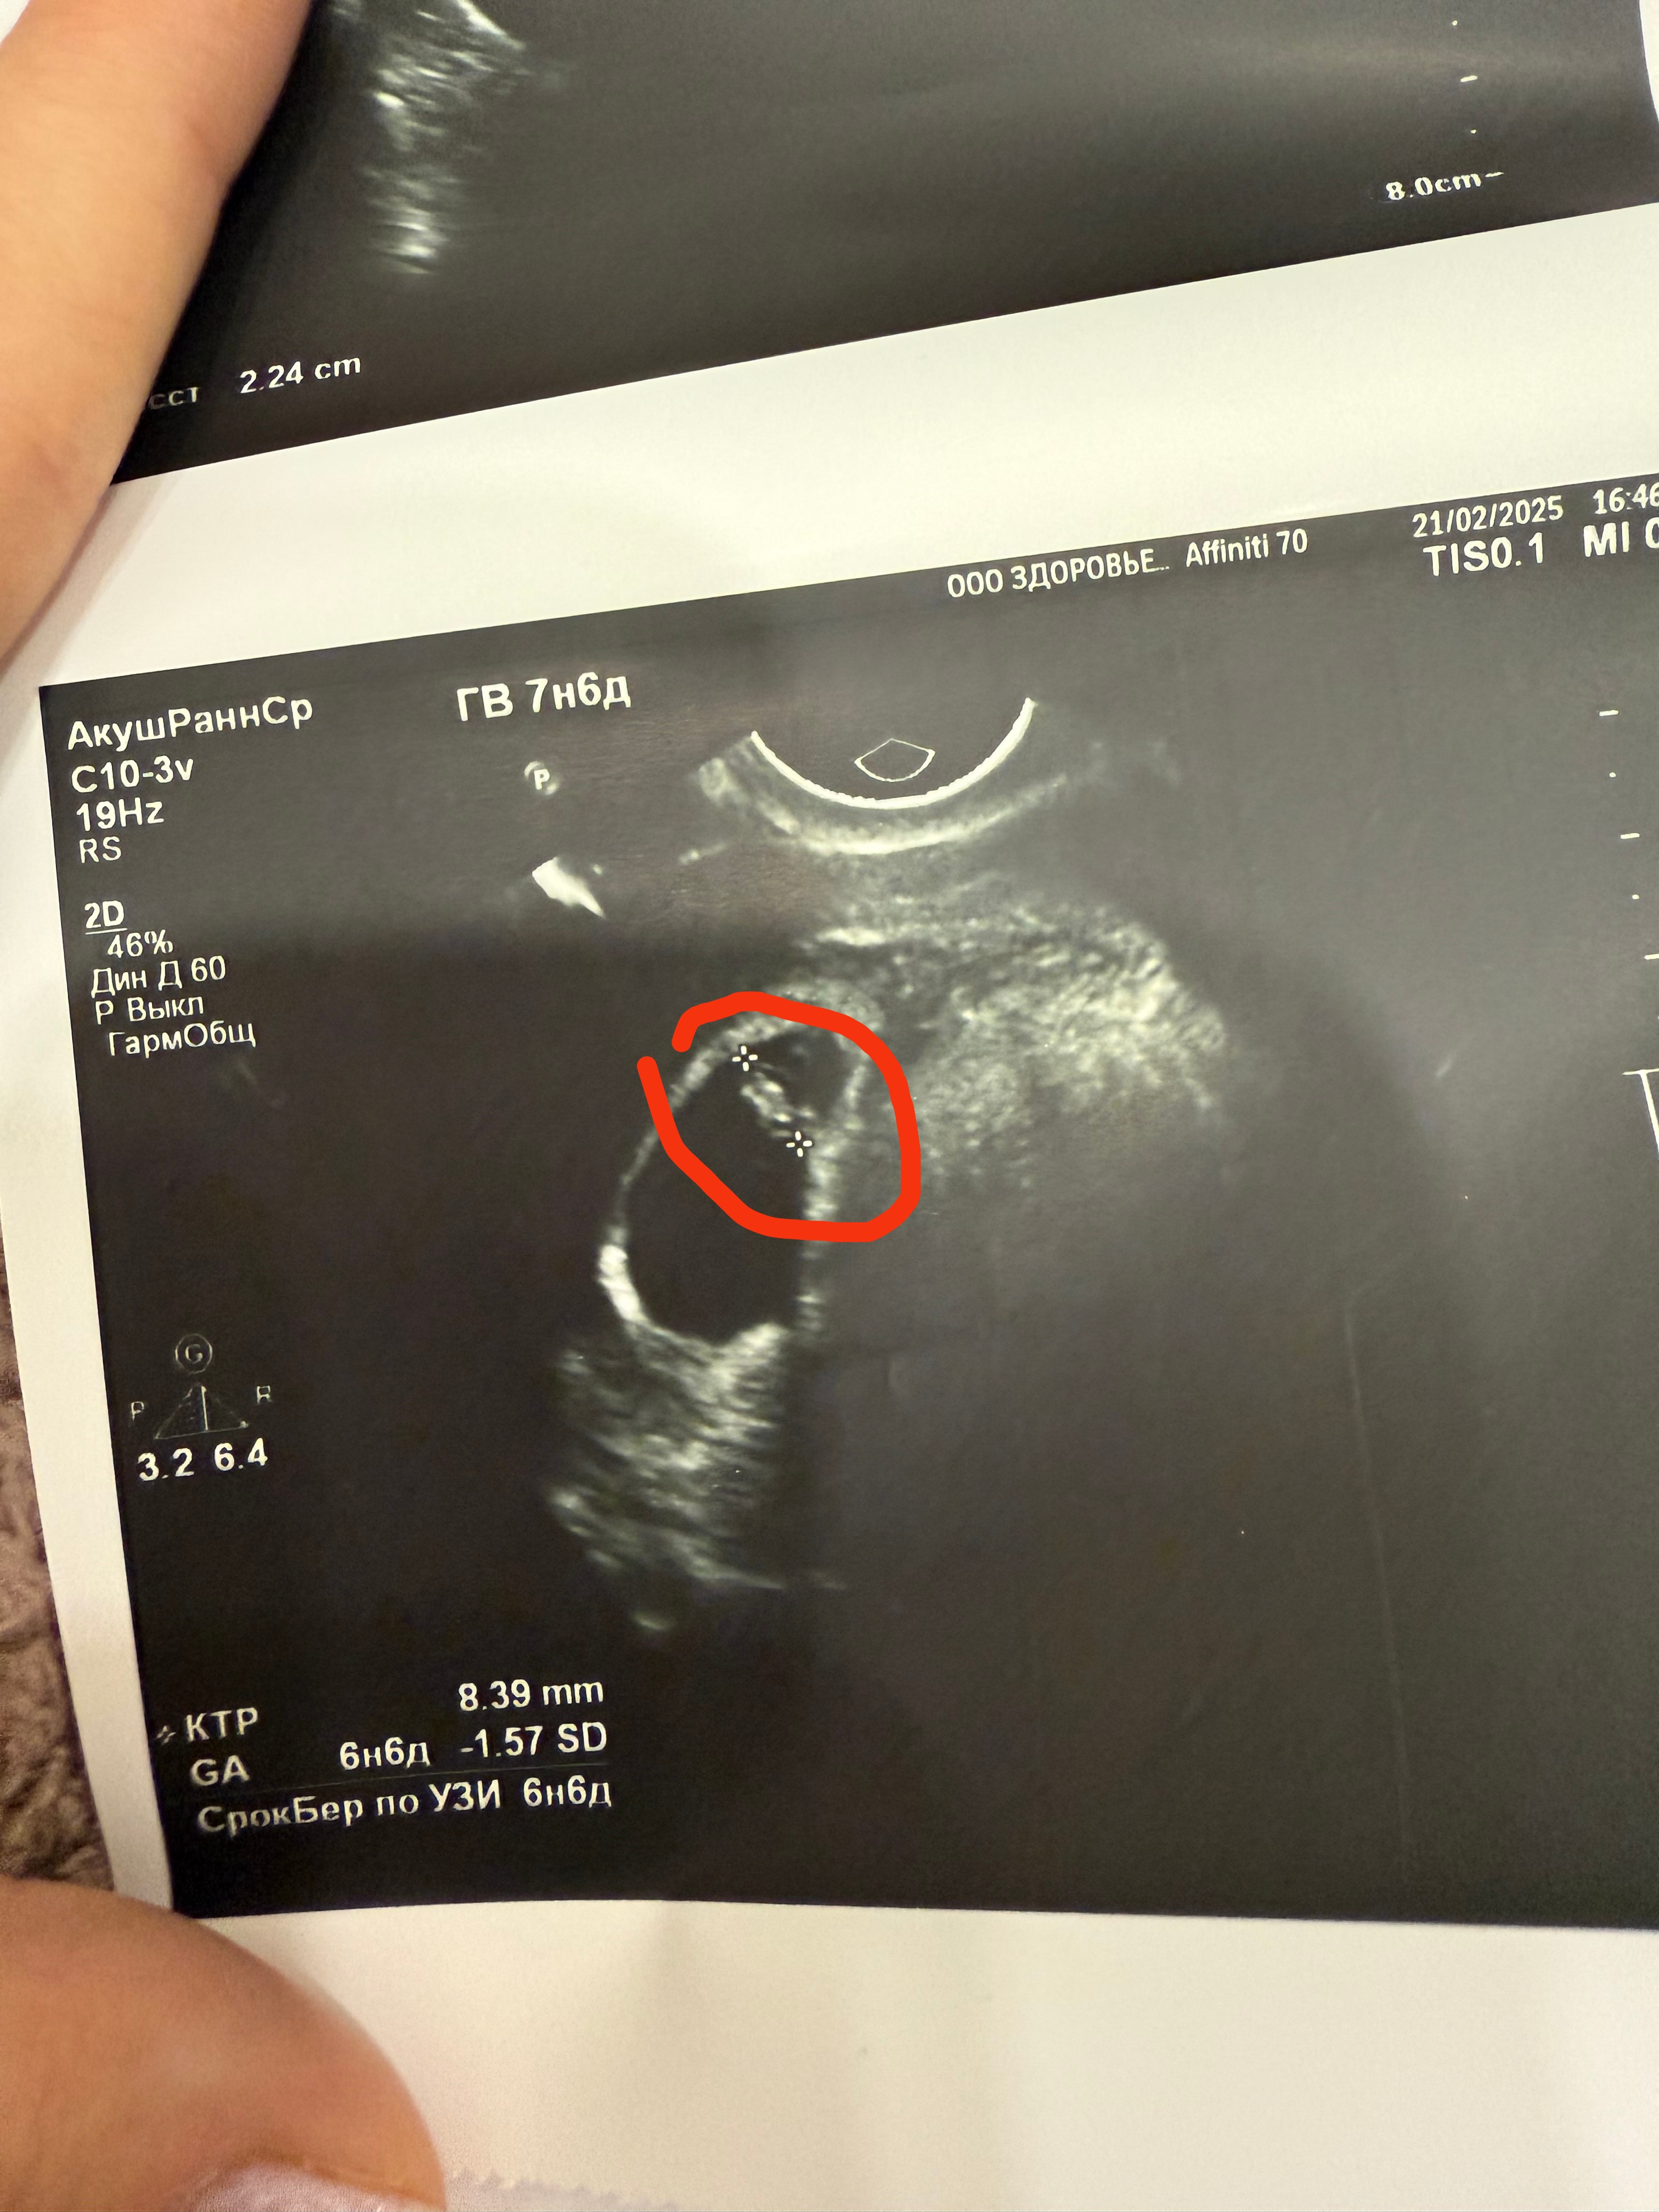

Вот эмбрион 8,4 мм Изображение